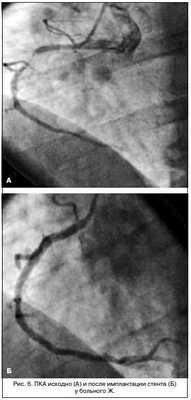

Коронарография: стеноз 70% проксимальной части ПМЖВ ЛКА, стеноз более 70% проксимальной трети правой коронарной артерии (ПКА). Тип кровоснабжения — правый (рис. 5).

Проведены дилатация и стентирование суженных участков ПМЖВ ЛКА и ПКА с удовлетворительным ангиографическим эффектом (рис. 6).